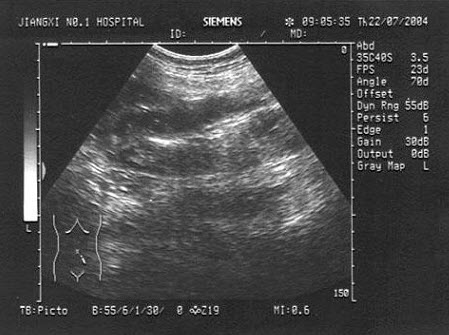

49、多项选择题 放射免疫分析的必备条件是()

“火海征”是何种甲状腺疾病的声像图特征()

①毒性甲状腺肿

②结节性甲状腺肿

③慢性淋巴性甲状腺肿

④地方性甲状腺肿

A.①②

B.②④

C.③④

D.①③

E.①②③④